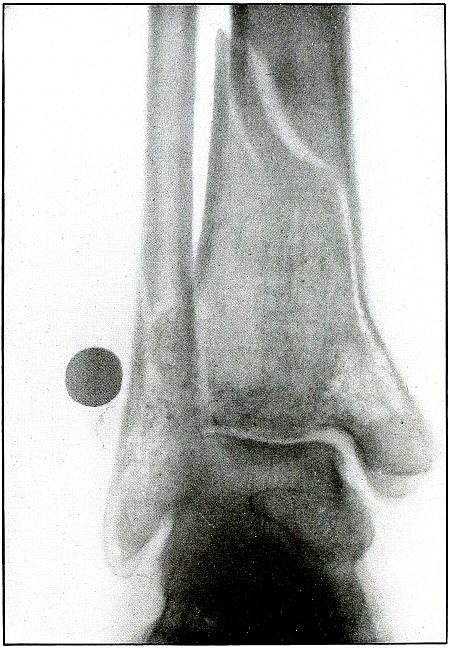

Gunshot fracture, ankle |

154 |

| 73. |

Gunshot wound, heel |

156 |

| 74. |

Gunshot wound, heel |

158 |